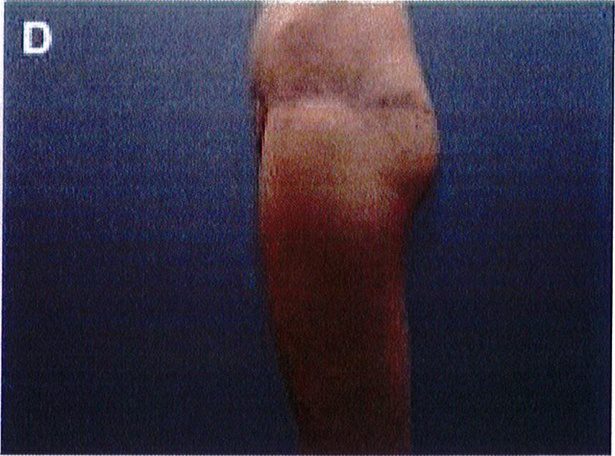

Sau phẫu thuật cần băng lại vết mổ, dùng loại băng dài khoảng 1 inch. Băng này sẽ được tách thành nhiều sợi nhỏ chiều rộng khoảng 3-4 cm (nhưng hai đầu dây không tách rời, tức vẫn là 1 dải băng lớn được tách nhỏ ra) nhằm có thể mở rộng dải băng, Đồng thời hạn chế lực ép vì nguy cơ tụ máu và tăng sắc tố sau phẫu thuật. Không sử dụng các loại băng ép vì chúng có thể ép làm tách đôi vết mổ. Sau phẫu thuật, chúng tôi cho bệnh nhân ngồi nhẹ nhàng trên gối hoặc đệm mềm, nằm nghiêng. Vùng phẫu thuật được kiểm tra thường xuyên trong thời gian chăm sóc hậu phẫu để đảm bảo vết thương lành

Sau phẫu thuật không nên đóng ngay mà nên dùng ghim da, ghim tạm thời vết mổ lại. Sau đó dùng chỉ khâu vicryl số 0 hoặc số 1 khâu gá lớp cân nông bằng các mối rời để kéo hai mép da lại gần với nhau. Sau đó đóng lớp hạ bì bằng chỉ vicryl 2-0, lớp biểu bì bằng chỉ monocryl 4-0. Ngoài ra, để đảm bảo không bị tách vết mổ, nên khâu da bổ sung thêm bằng một sợi prolene 3-0 mối rời (Hình 10). Mặc dù khâu nhiều loại và nhiều lớp chỉ như vậy nhưng sau khoảng 4-5 ngày cắt chỉ